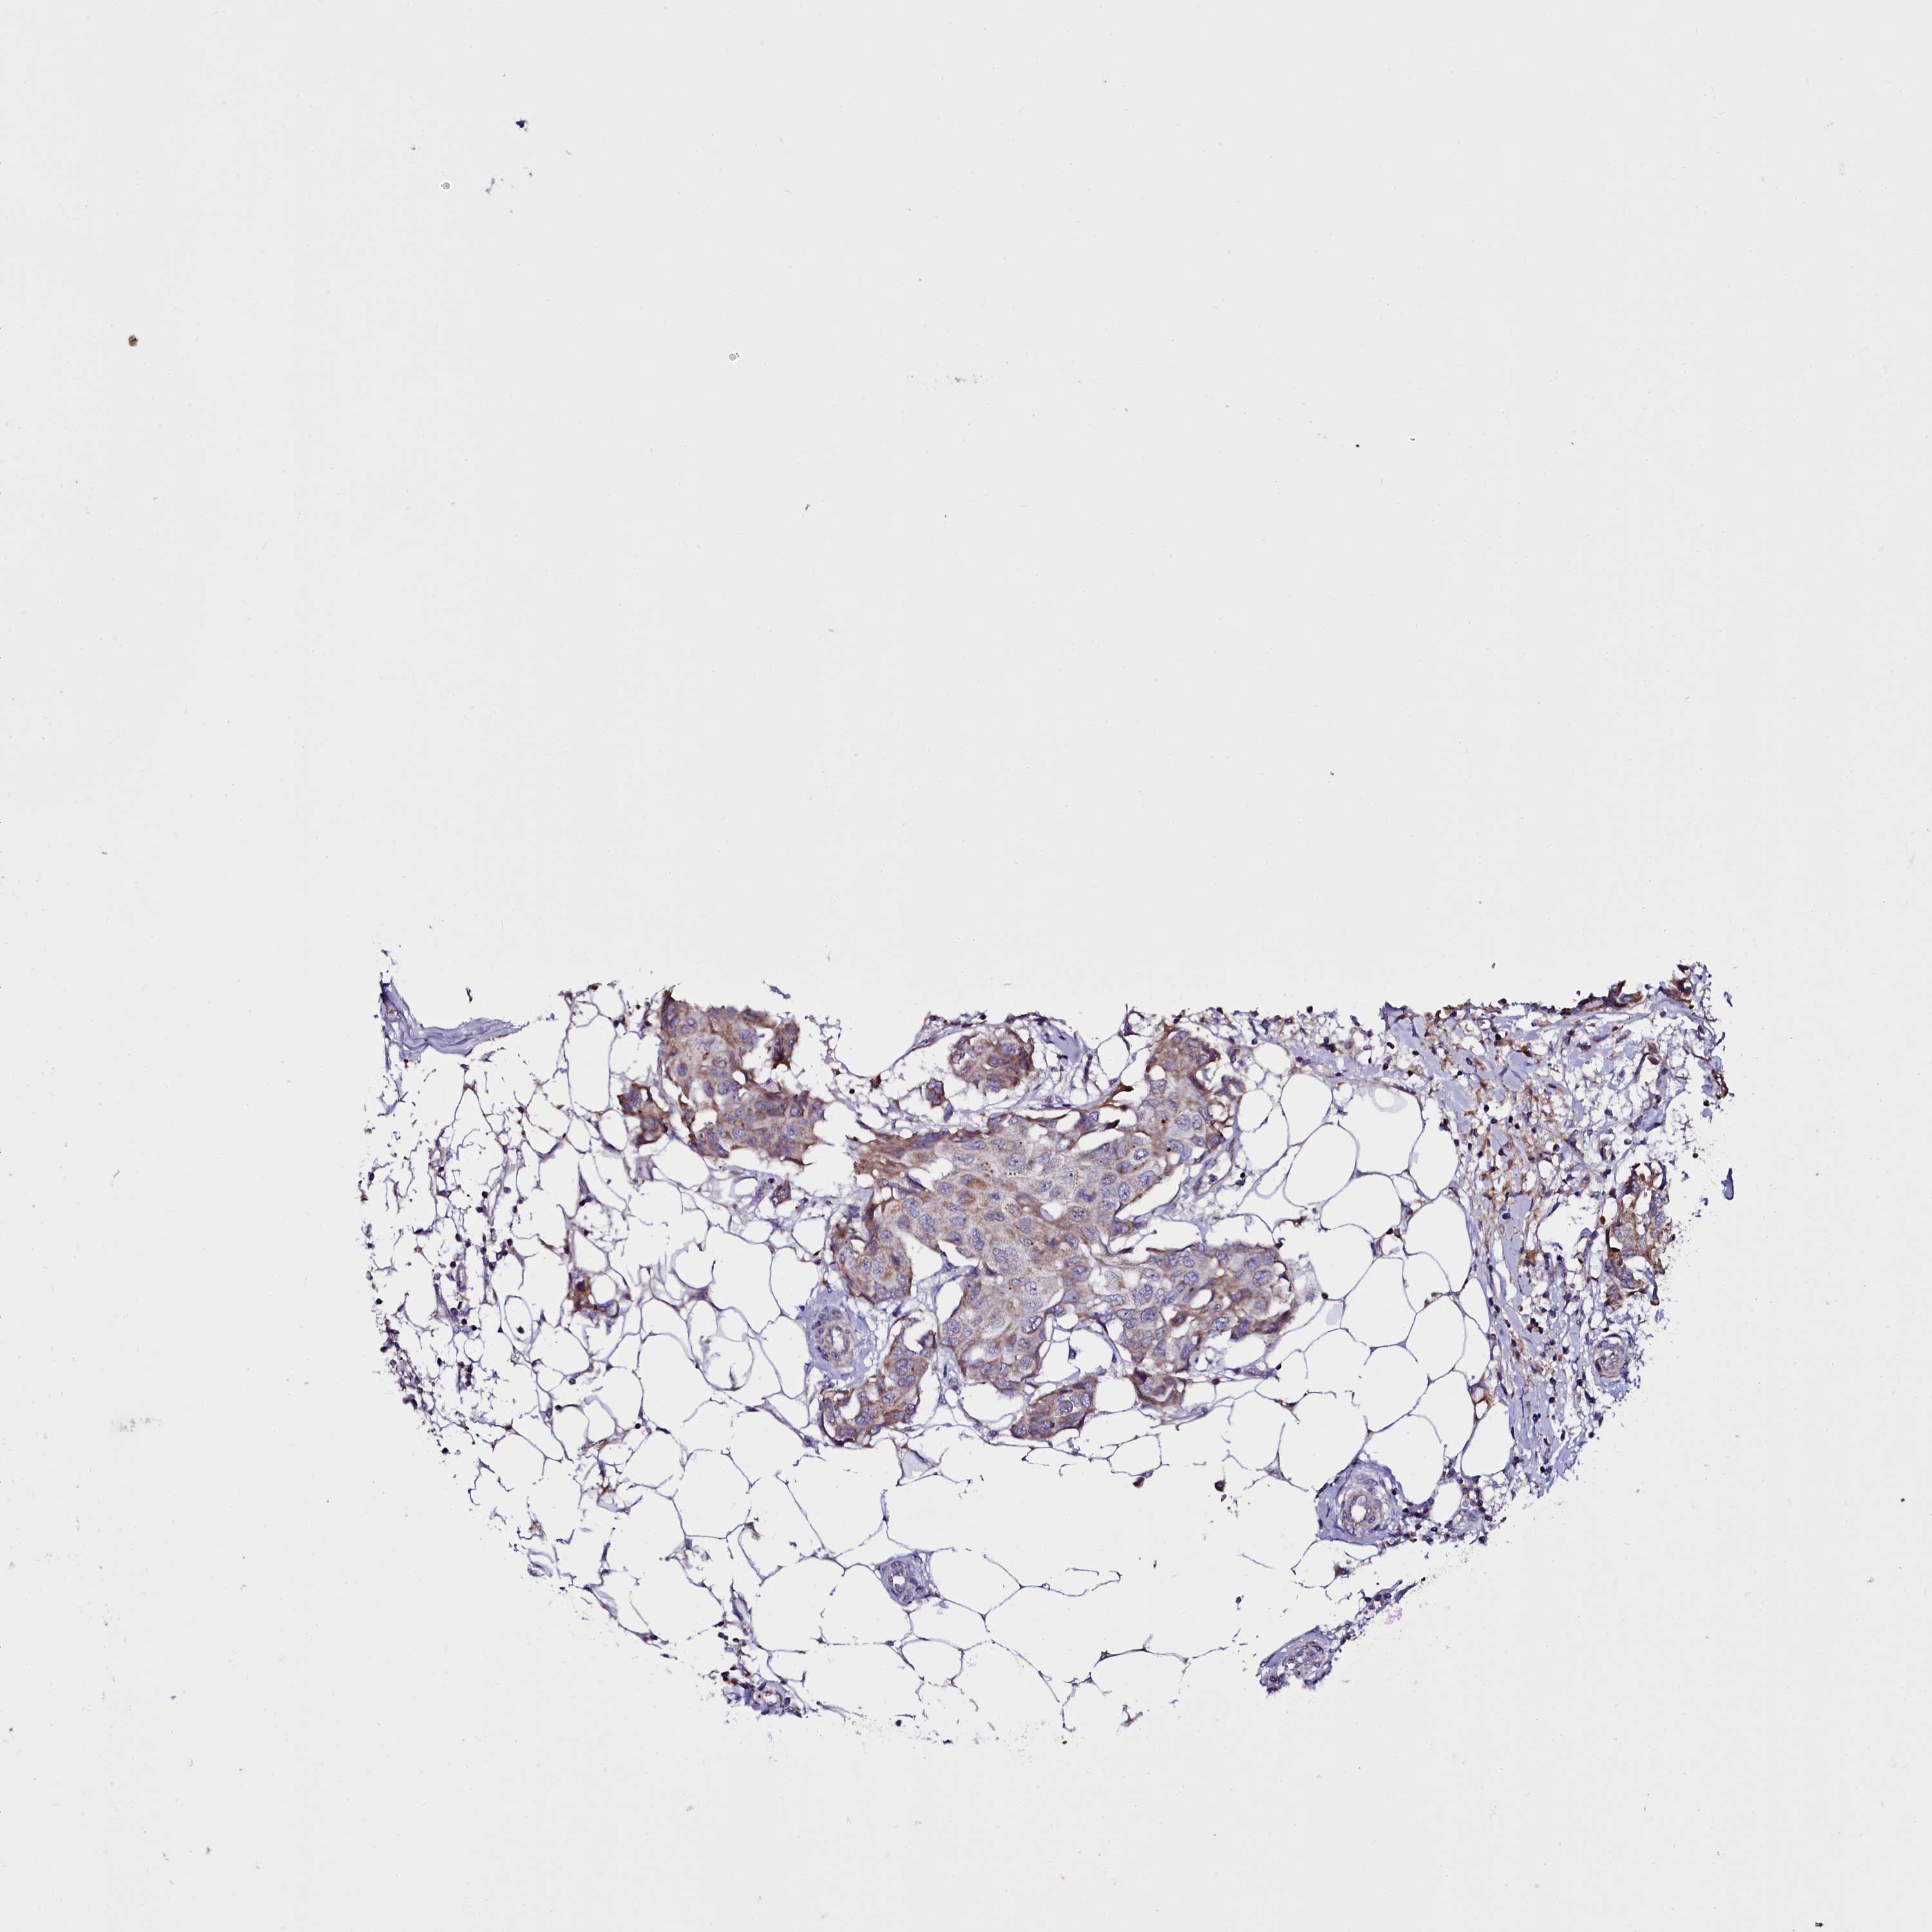

CANCER BREAST CANCER Show tissue menu

BRCA TCGA BRCA VALIDATION PROTEIN EXPRESSION